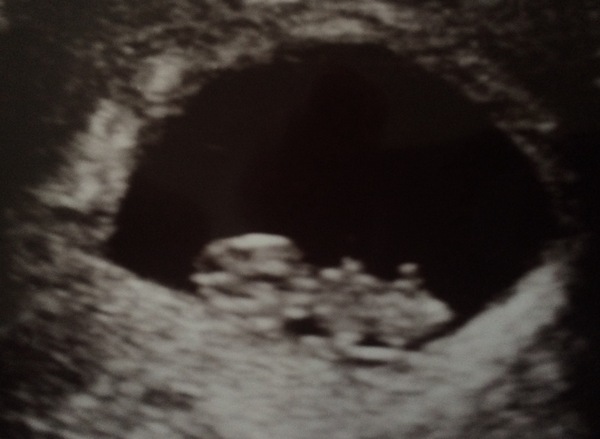

mrskitty15 · 17/08/2017 12:16

Hello ladies, Our scan went well, the dates are slightly different from what we had worked out from my LMP date so it is actually measuring at 8+1 not 9+2 like we thought, but I think that is fairly standard (fingers crossed). The heartbeat was strong and normal. All looking good so far 😊

whyhastherumgone · 17/08/2017 12:46

Great news @Mrskitty15 ours went well too although yours looks more baby like, ours was more a blob! He dated us slightly earlier too i thought i was 8 + 5 but hes put me closer to 8. measuring 17.5mm with a flickering heart beat - he didn't give us heart rate but said everything was looking good (it didn't look that fast to me while i was watching but the blob kept moving around and hiding so it was hard to see).

Yay!! So pleased your scans went well, @whyhastherumgone @mrskitty15 and @WiIdfire ! 😊 I also had mine this morning. They said 12+4 which moves me one day later than last scan to 25th Feb.. I'll update the Google doc when I'm on a computer, thanks for that @DancingUnicorn must've taken ages!

It wiggled and waved at us then turned it's back when it'd had enough prodding and poking and the sonographer said everything looked good, nuchal thing was fine etc 💕💕 I'm so relieved I've seen a heartbeat cos I've barely had any symptoms recently but now it really feels real 🙊 not twins though this time! 😜

That sounds lovely and positive @HappyHippy. Very clear scan for you too, your baby looks very comfy in there.